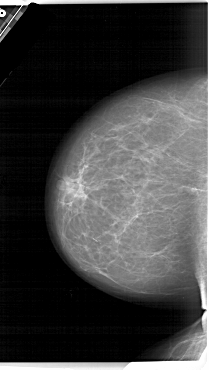

A_1464_1.LEFT_MLO

LEFT_MLO LINES 6031 PIXELS_PER_LINE 3631 BITS_PER_PIXEL 12 RESOLUTION 43.5 OVERLAY